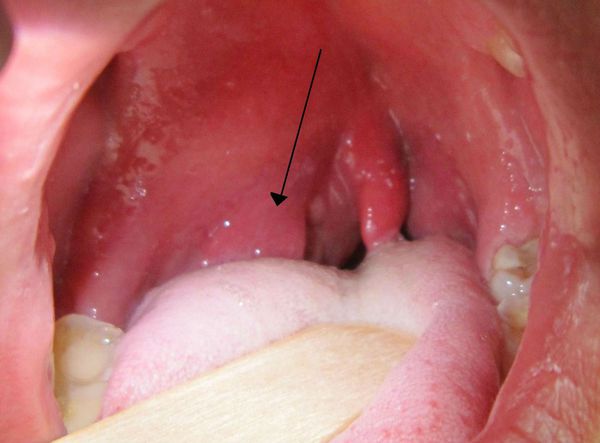

Тонзилогенный абсцесс полости рта